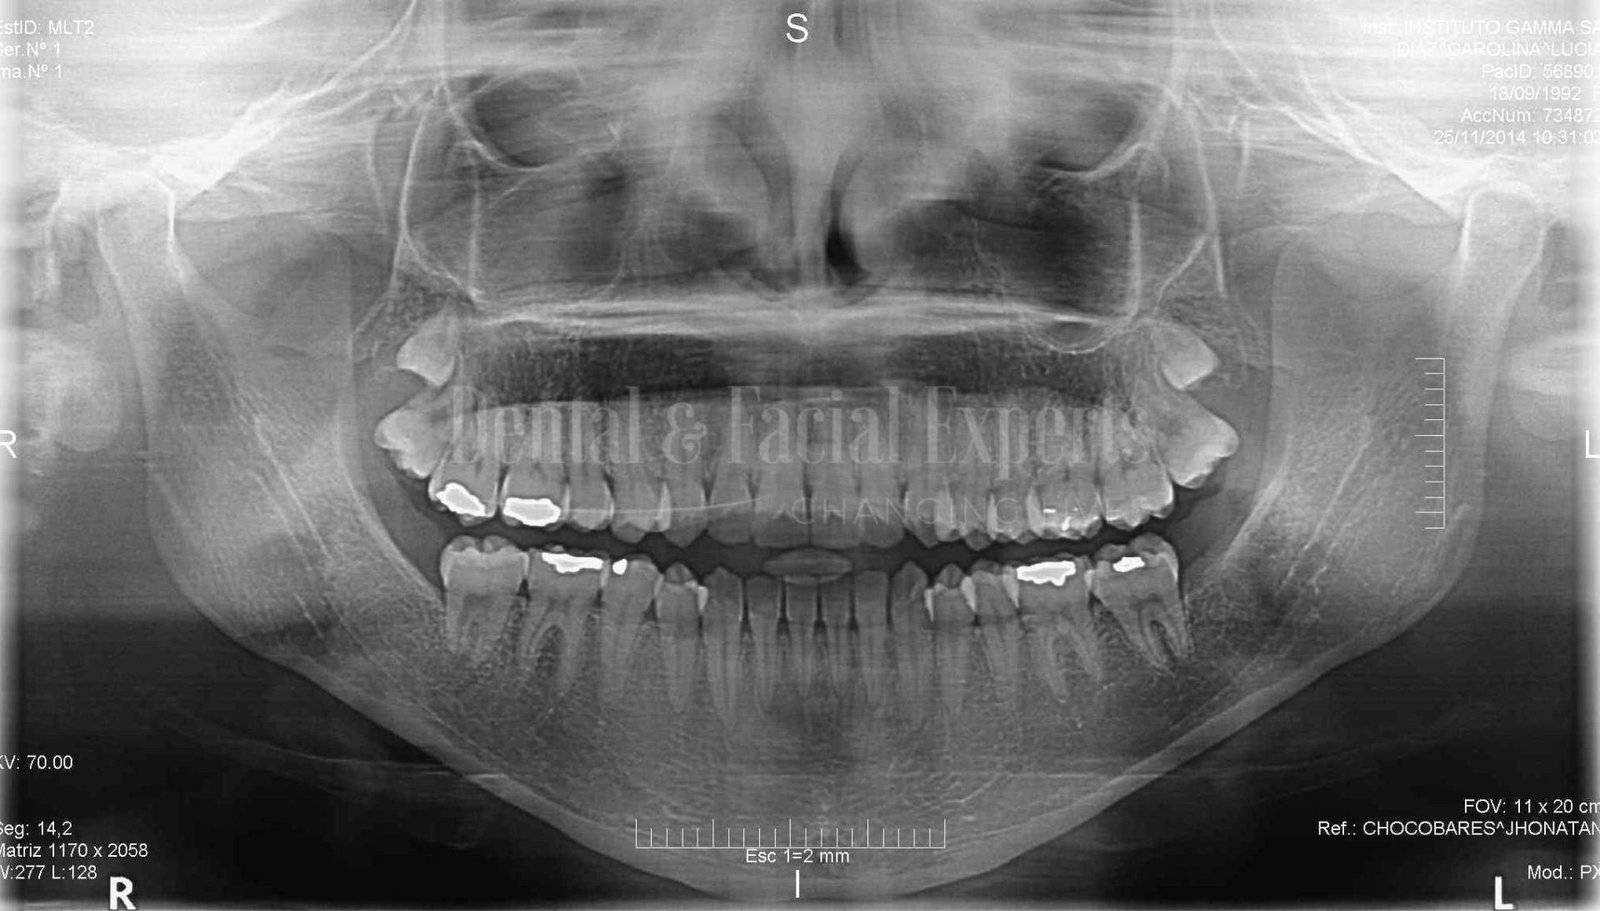

La cirugía maxilofacial es una especialidad médico-quirúrgica que aborda patologías, malformaciones y traumatismos de la cara, mandíbula, maxilares, boca y cuello. Su objetivo es restaurar la funcionalidad y mejorar la estética facial, abarcando procedimientos tanto reconstructivos como cosméticos.